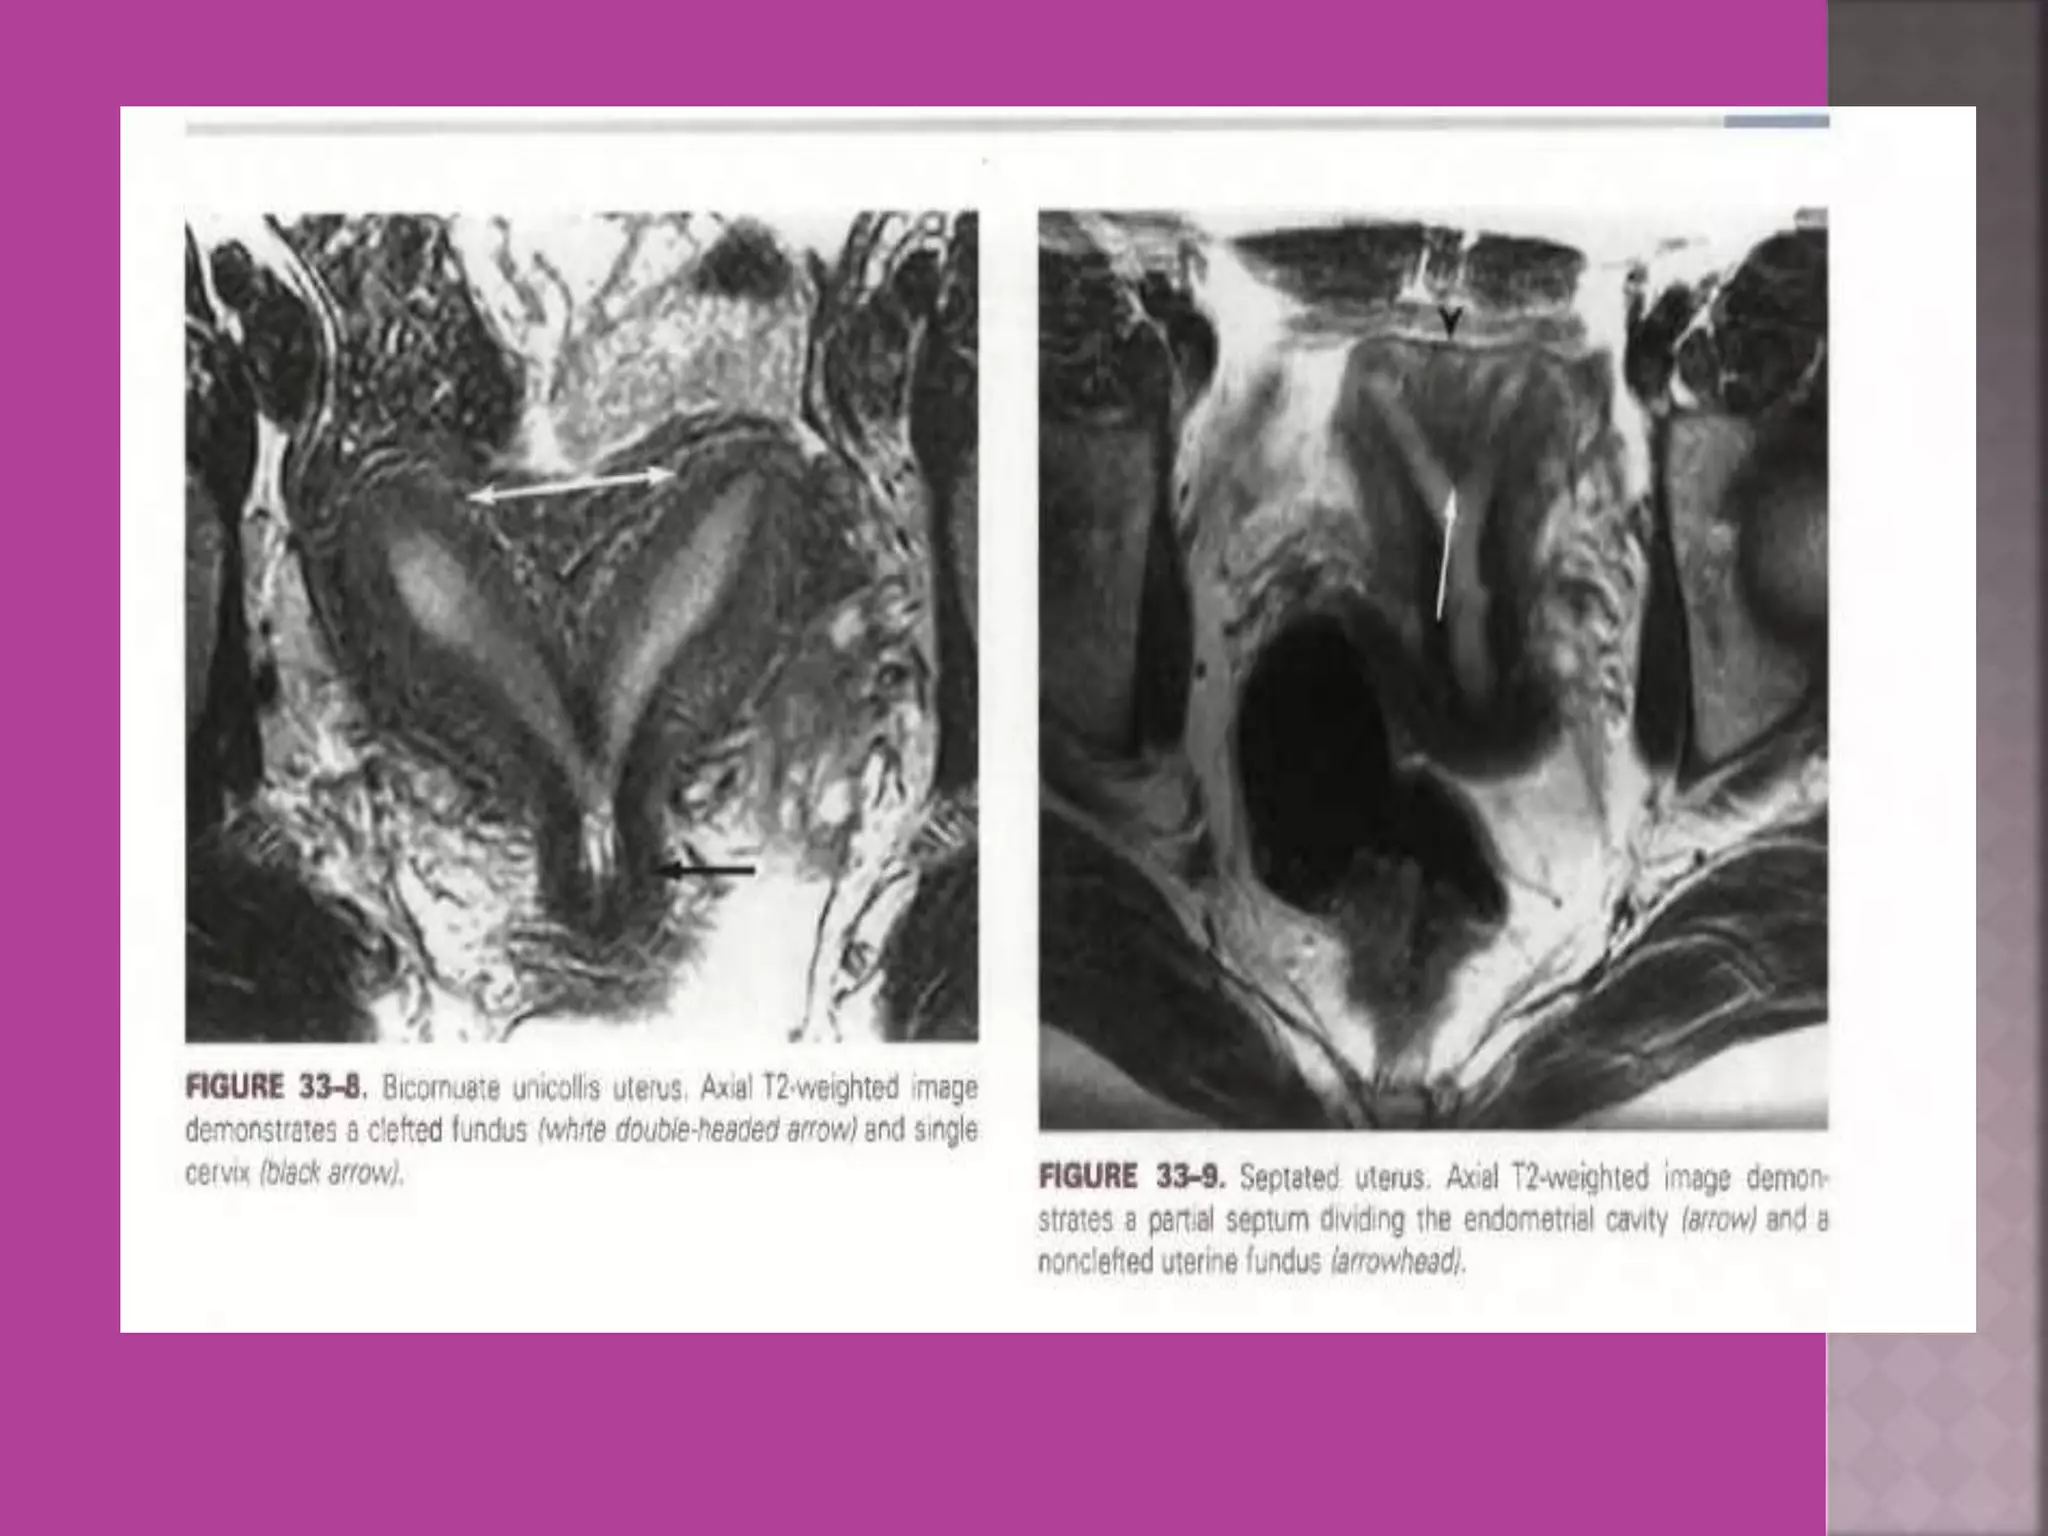

 Congenital uterovaginal anomalies—

bicornuate, septate,subseptate ,

unicornuate, didelphys ,rudimentary horn

and vaginal atrasia etc

 Study ofnormal uterus and adnexa – with aim to have clear image of normal myometrium, endometrium , ovary and follicles within the ovary.  Myoma—to differentiate myoma from adenomyoma.localization of myoma—sub serous/ intra mural or sub mucous.  Adenomyosis---accurate diagnosis.  Congenital uterovaginal anomalies— bicornuate, septate,subseptate , unicornuate, didelphys ,rudimentary horn and vaginal atrasia etc